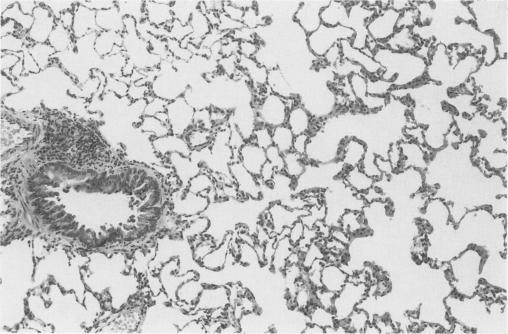

Using a left lung orthotopic isograft model in adult male AS strain rats, the pathology of lungs which were stored for 48 or 72 hours using a simple organ flush technique followed by low temperature (0 degrees C) immersion has been investigated. Lungs were examined after cold storage alone and after storage followed by either brief (up to 1 hour) or extended (30 days) reperfusion with blood in vivo. Grafts were flushed with either isotonic saline (NaCl) or hypertonic citrate solution (HCA) alone, or with HCA containing either verapamil (a Ca(2+)-channel blocker) or prostacyclin (PGI2 which has both anti-platelet and vasodilator actions). Controls included fresh non-flushed lungs and fresh HCA-flushed lungs which were transplanted immediately after harvest. After prolonged (48 or 72-hour) cold ischaemia alone the only clear change in lung morphology was of nuclear swelling. Early reperfusion changes included: (i) oedema (interstitial and alveolar); (ii) vascular congestion; and (iii) intra-alveolar haemorrhage. Features (i) and (ii) were diffuse whilst haemorrhage was patchy. Lungs which remained in vivo for up to 30 days showed focal scarring and chronic inflammation with numerous macrophages containing haemosiderin; the extent of the changes observed in individual grafts tended to mirror the gross macroscopic outcome. Attempts to improve the cold ischaemic tolerance with added agents (verapamil and prostacyclin PGI2) failed to produce a clear advantage.

在成年雄性AS品系大鼠中使用左肺原位同种异体移植模型,研究了采用简单器官冲洗技术后在低温(0摄氏度)浸泡下保存48或72小时的肺的病理学情况。在单纯冷藏后以及冷藏后分别在体内进行短时间(长达1小时)或长时间(30天)血液再灌注后对肺进行检查。移植物分别用等渗盐水(NaCl)或单纯高渗柠檬酸盐溶液(HCA)冲洗,或用含有维拉帕米(一种钙通道阻滞剂)或前列环素(PGI2,具有抗血小板和血管舒张作用)的HCA冲洗。对照组包括新鲜未冲洗的肺和收获后立即移植的新鲜HCA冲洗的肺。仅在长时间(48或72小时)冷缺血后,肺形态学上唯一明显的变化是细胞核肿胀。早期再灌注变化包括:(i)水肿(间质和肺泡);(ii)血管充血;以及(iii)肺泡内出血。特征(i)和(ii)是弥漫性的,而出血是散在的。在体内保留长达30天的肺显示局灶性瘢痕形成和慢性炎症,有许多含铁血黄素的巨噬细胞;在单个移植物中观察到的变化程度往往反映总体宏观结果。尝试用添加药物(维拉帕米和前列环素PGI2)提高冷缺血耐受性未能产生明显优势。